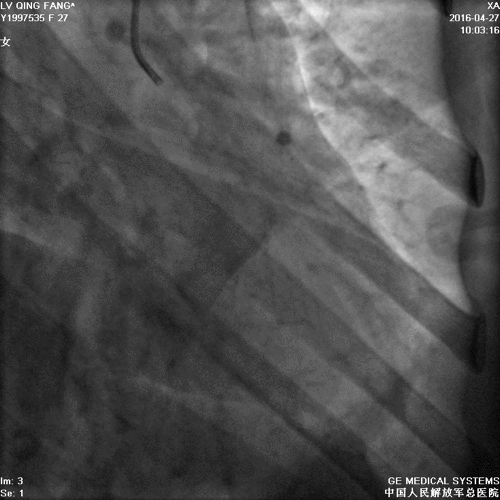

造影

PCI